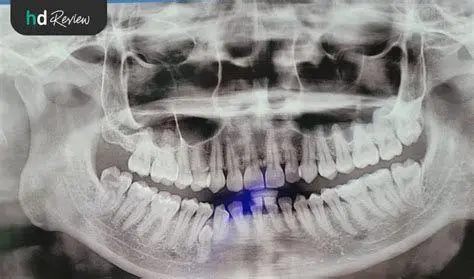

- Rontgen Panoramik dan Cephalometric: Diperlukan untuk melihat struktur tulang rahang dan akar gigi sebelum prosedur dimulai (Estimasi Rp 500.000 - Rp 1.000.000).